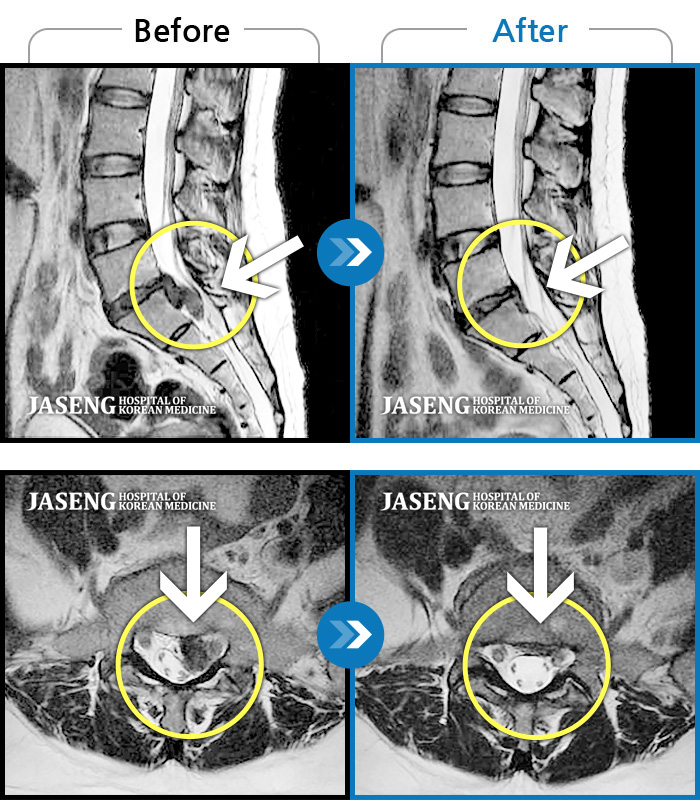

허리디스크

잠실 · 한상욱 원장

허리가 많이 아프고 왼쪽 다리가 저려 움직이기가 힘들다.

촬영시기

2022.01.19 ~ 2022.11.14

2022.12.02